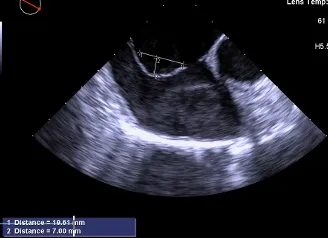

测量膨出瘤基底宽19.61mm,深7.00mm

房间隔总长44.22mm,缺损大小14.80mm